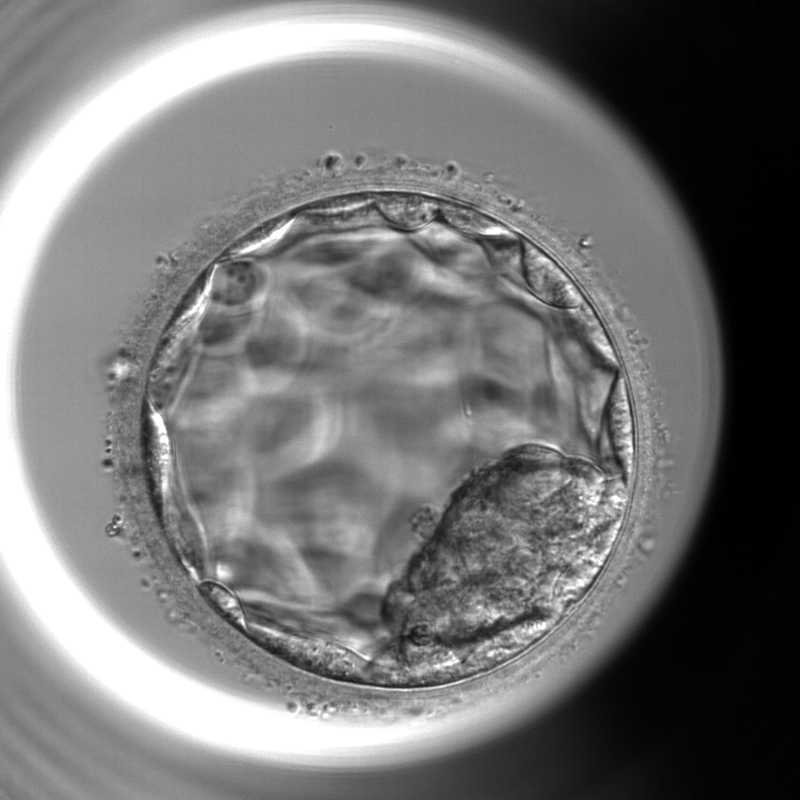

胚培養とは?採卵後の受精卵の発育

胚培養とは 体外受精では、採卵した卵子と精子を受精させたあと、受精卵(胚)を培養器の中で発育させます。この過程を「胚培養」といいます。受精卵は分割を繰り返しながら発育し、通常は採卵から5〜6日ほど培養されます。培養2〜3日目の初期胚で移植する場合もありますが、多くの場合は培養5日目頃の胚盤胞まで発育させて移植や凍結を行います。 採卵後の胚の発育(培養0日目〜6日目) 採卵後、受精した胚(受精卵)は細胞分裂を繰り返しながら発育していきます。体外受精では、この発育過程を培養器の中で管理しながら観察していきます。胚の発育は採卵日を培養0日目(Day0)として数え、通常は培養5日~6日目(Day5〜Day6)頃まで培養され、それぞれの段階で胚の状態を観察し、発育状況を確認します。 培養0日目(Day0) 採卵・受精 採卵したての卵子には、成熟の段階によっていくつかの状態があります。 GV期卵(Germinal Vesicle) 第一減数分裂前期の卵子で、まだ成熟していない状態です。LHサージによって成熟が再開します。 MⅠ期卵(MetaphaseⅠ) 第一減数分裂中期の卵子で、未成熟卵に分類されます。採卵当日中に成熟が確認できれば受精が可能となります。 MⅡ期卵(MetaphaseⅡ) 第二減数分裂中期の卵子で、成熟した卵子です。受精が可能な状態であり体外受精では主にこの段階の卵子を採取することを目標としています。 受精の確認には、極体(Polar Body:PB)という構造を観察します。成熟したMⅡ期卵は、第一極体が放出されている状態です。そして、受精後には第二極体の放出が確認されます。 培養1日目(Day1)受精確認(PNチェック) 採卵の翌日(培養1日目)には、卵子が正常に受精しているかを確認します。このときに観察するのが前核(PN:pronucleus)です。正常に受精した卵子では、卵子由来と精子由来の2つの前核が確認されます。これを2PNと呼び、正常受精の所見とされています。一方で、前核が1つしか見えない場合や、3つ以上確認される場合は正常受精ではない可能性があります。また、前核が確認できない場合もあります。 培養2〜3日目(Day2〜3)初期胚(分割胚)